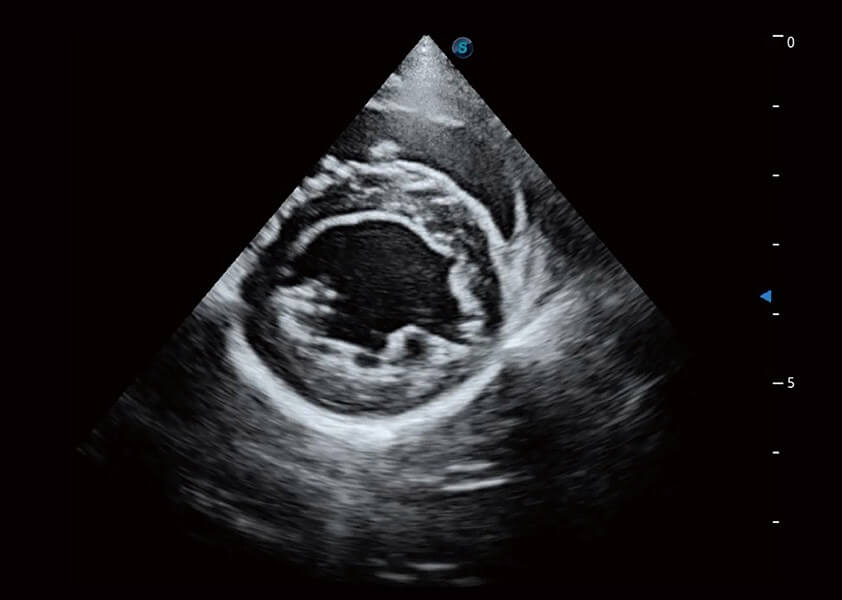

心脏解决方案

ProPet 60 配备了丰富的心脏探头群、先进的成像技术和专业的心脏测量工具,可帮助动物医生为不同体型和生理结构的动物提供心脏和心肌功能的全面评估。

(犬)乳头肌短轴